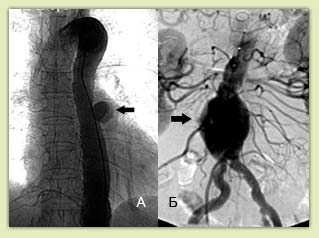

Рис.2 Ангиографическая картина:

a) мешотчатая аневризма грудной аорты

б) веретенообразная аневризма брюшной аорты

ангиография: позволяет выявить деформацию аорты и ее ветвей, однако истинные размеры аневризмы не всегда видны в связи с возможным наличием пристеночного тромбоза полости аневризмы

(рис.2).